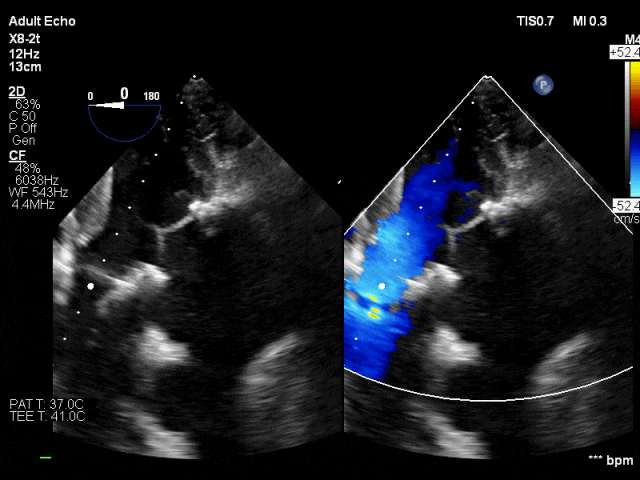

患者男性,68岁,主诉因“活动后胸闷、气促半年”入院,行心脏超声检查提示:主动脉瓣二瓣化畸形、狭窄 (重度)合并关闭不全(中-重度),二尖瓣狭窄并关闭不全(重度),左房明显增大。冠脉造影提示三支血管严重狭窄病变。吴钟凯教授经过周密的术前讨论与部署,联合麻醉科、手术室等多科室强大的协作实力,术中建立体外循环转机,首先完成冠状动脉旁路移植(LIMA-LAD,GSV-LCX; GSV-RCA);二尖瓣位植入M27佰迈思®限位可扩张二尖瓣生物瓣,主动脉瓣位置入A21佰迈思®限位可扩张主动脉瓣生物瓣。心超提示:冠心病CABG+DVR术后,人工主动脉瓣及人工二尖瓣功能良好,人工主动脉瓣测其平均压差5mmHg,人工二尖瓣测其平均压差3mmHg。瓣膜功能表现出色,患者术后恢复良好。